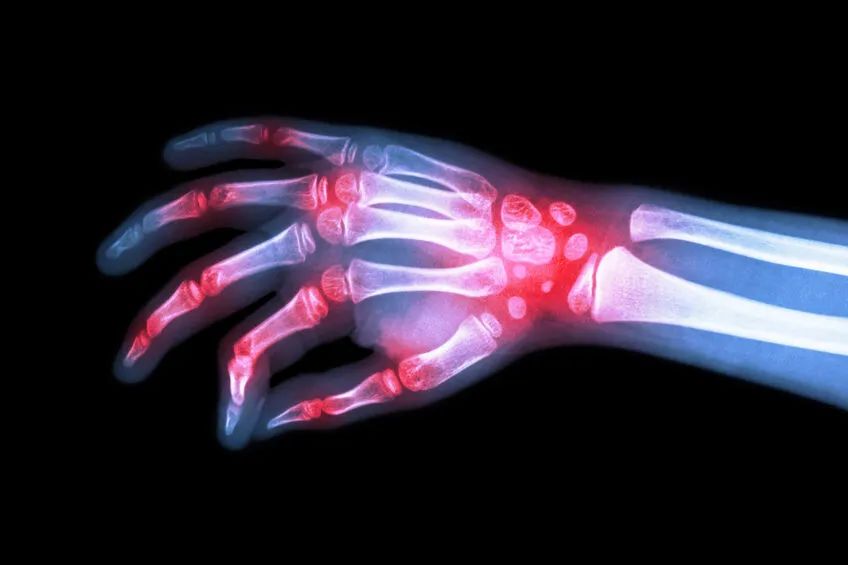

骨关节炎是中老年最常见的慢性关节疾病之一,是以关节疼痛为主要临床表现,同时可伴有晨僵、关节肿大、骨擦音以及关节活动受限,晚期可出现关节畸形等。

关节肿大

关节肿大常见于指间关节的骨关节炎,而晚期的膝关节骨关节炎也会出现关节肿大,与关节内骨赘(骨刺)生成、软组织肿胀及关节积液有关。